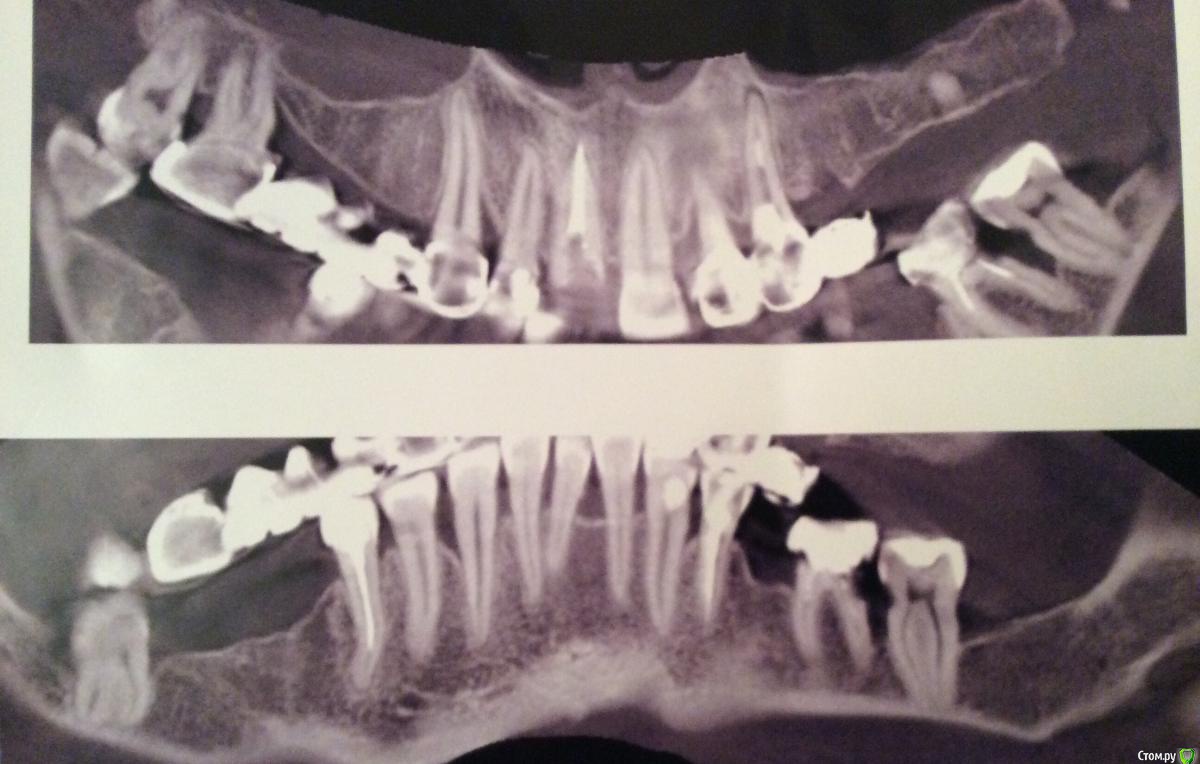

syrovovec Опубликовано 5 марта, 2015 Поделиться Опубликовано 5 марта, 2015 Обратилась пациентка с желанием получить кусочек титана в кость. В полости рта штампованные коронки, подвижности зубов нет, карманы от 3 до 7 мм, гноя нет, ремиссия.последнее обострение год назад, лечилась полосканиями. Изначально вопрос стоял по третьему сегменту, сейчас хочет все.Внимание вопрос:так как пародонтолога нет в принципе, то я за него. В какой последовотельности? Удалять кюретажить крутить. медикаментозно что?11 ортопед сохраняет,все остальное можно сносить.Панорама пока такая, не могу в новом ez разобраться Ссылка на комментарий

syrovovec Опубликовано 5 марта, 2015 Автор Поделиться Опубликовано 5 марта, 2015 (изменено) Мысли: 17 ,36,37 удалить13,22,32,43 кюретажНижний фронт под вопросомМогу фотки завтра скинуть если нужно Изменено 5 марта, 2015 пользователем syrovovec Ссылка на комментарий

krokomot Опубликовано 5 марта, 2015 Поделиться Опубликовано 5 марта, 2015 У пациентки вертикальные костные карманы это говорит о значительнгой функциональной перегрузкеЯ бы сделал так:1 гигиена, кюретаж если есть грануляции пока глубоко не лезть2 удаление явно ненадёжных зубов3 изготовление сьемноно протеза до нормализации уровня кости4 попутное эдодонтические мероприятия, где требуется5 через 3 месяца повторная гигиена с кюретажем, где требуется (после снимка конечно)все это сопровождается отличной индивидуальной гигиеной полости рта с аппликациями метрогила, приемом препаратов кальцияПосле этого можно говорить об имплантации, но не по этому снимку)) 1 Ссылка на комментарий